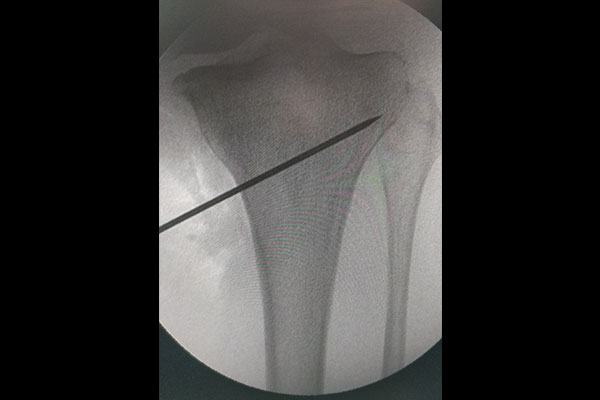

STEPS OF HTO